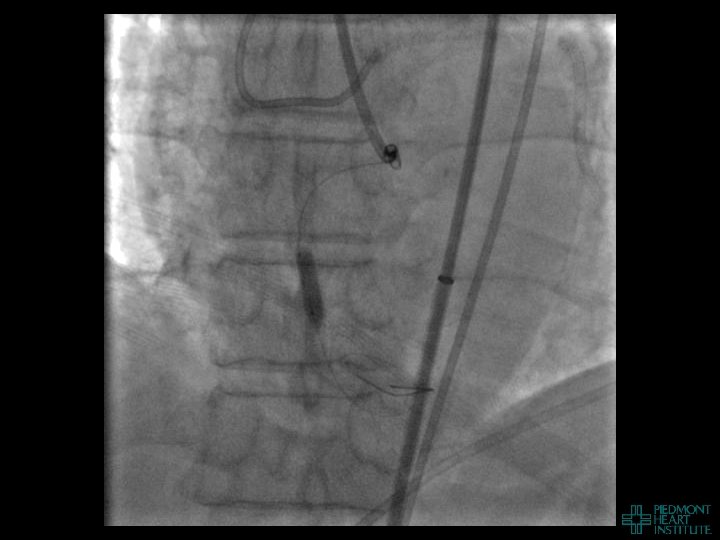

Case Example 4